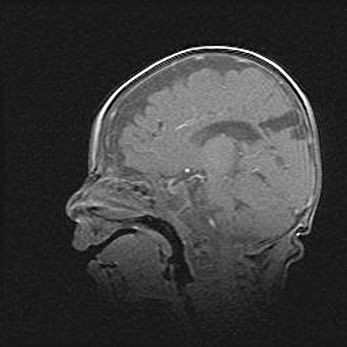

Церебральная ишемия II.

Возраст: 5 дней

Вес: 3400 г

Пол: женский

Окружность головы: 35 см

Срок гестации: 39 недель

Церебральная ишемия – это заболевание, характеризующееся недостаточностью (гипоксией) либо полным прекращением (аноксией) снабжения мозга кислородом по причине закупорки одного или нескольких сосудов. Это приводит к  что метаболическим расстройствам различной степени тяжести в тканях головного мозга, развитию коагуляционных некрозов и гибели нейронов.